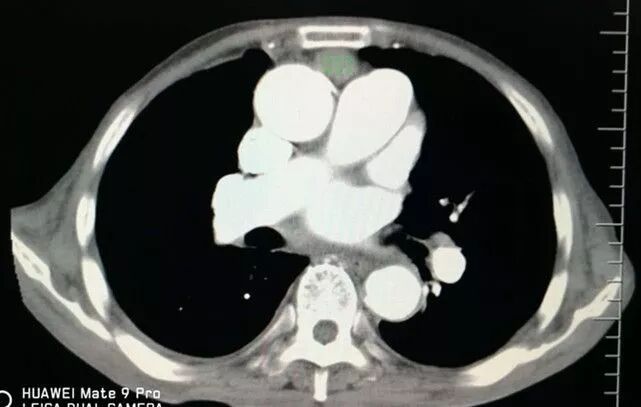

增強掃描顯示病灶與大血管關系密切!難度大、風險高!但沒有其它檢查手段或設備可替代穿刺活檢。

前有胸骨C,后有主肺動脈A、B,兩側有胸廓內動脈D、E遮擋,形成合圍之勢。

選擇右成角入路,穿越胸骨與主動脈間隙,該間隙僅僅10mm,并避開右胸廓內動脈,精細操作,先置入導針

再置入16G切割活檢槍,稍有偏差便可導致升主動脈損傷破裂,導致災難性后果發(fā)生。